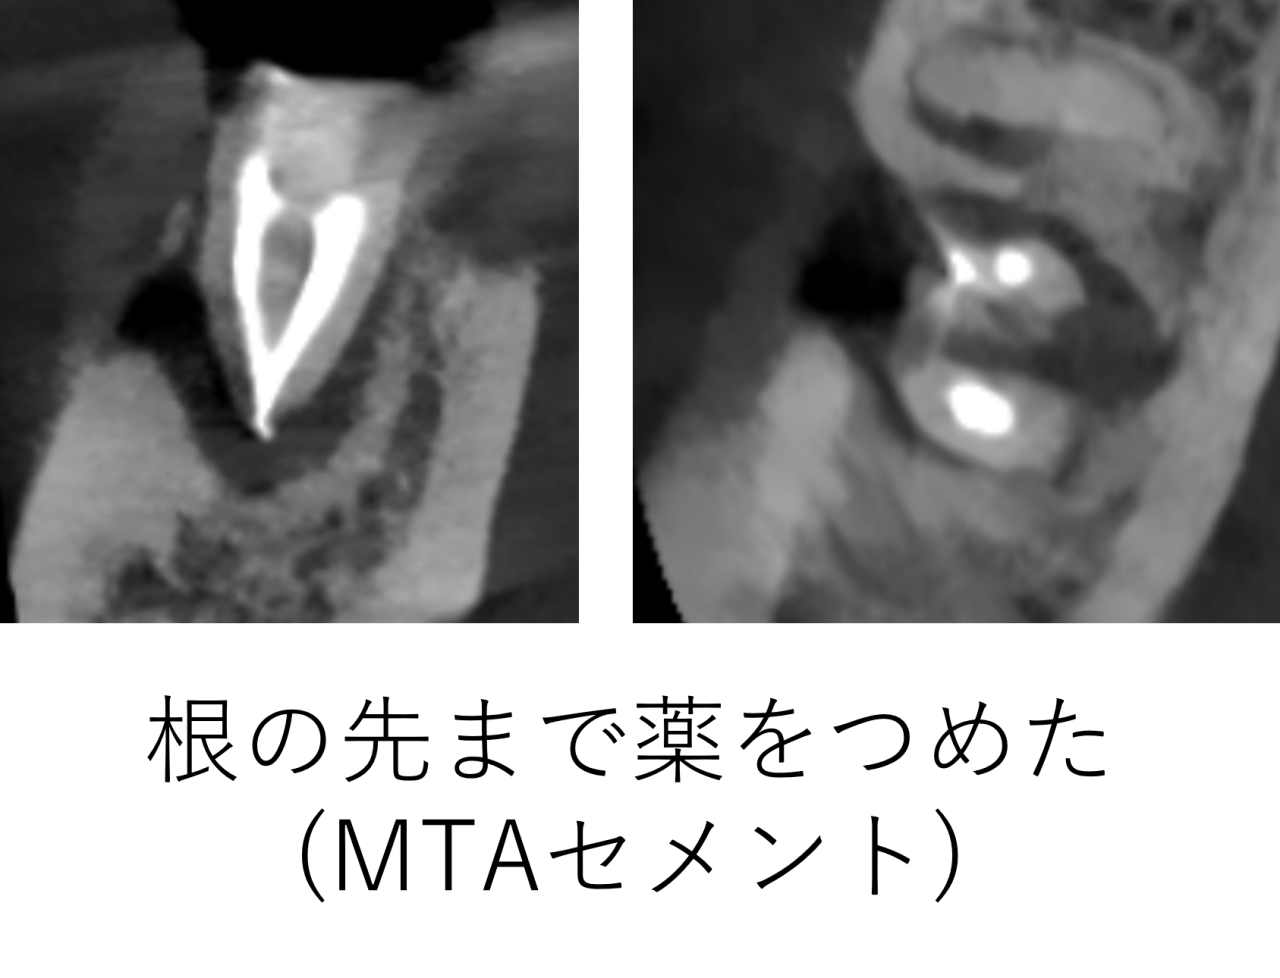

超音波洗浄を行い根がきれいになったところで、薬(MTAセメント:バイオセラミックス系の薬)をつめました。つめた後のレントゲンです。薬は白く映ります。根の先の方まで薬がつまっていることが確認できました。